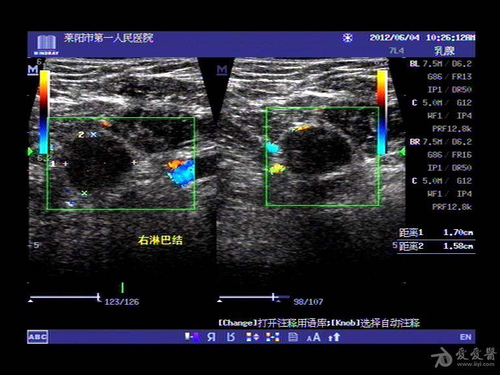

女性腋窝淋巴结肿大有可能是乳腺疾病引起的,不过这种情况比较少见。若是因乳腺疾病而引起女性腋窝淋巴结肿大,可将之称为乳腺增生伴淋巴结发炎。一般来说,只有女性出现乳腺疾病后,没有及时接受治疗,加上平时没有做好护理工作,才会导致淋巴结肿大发生。